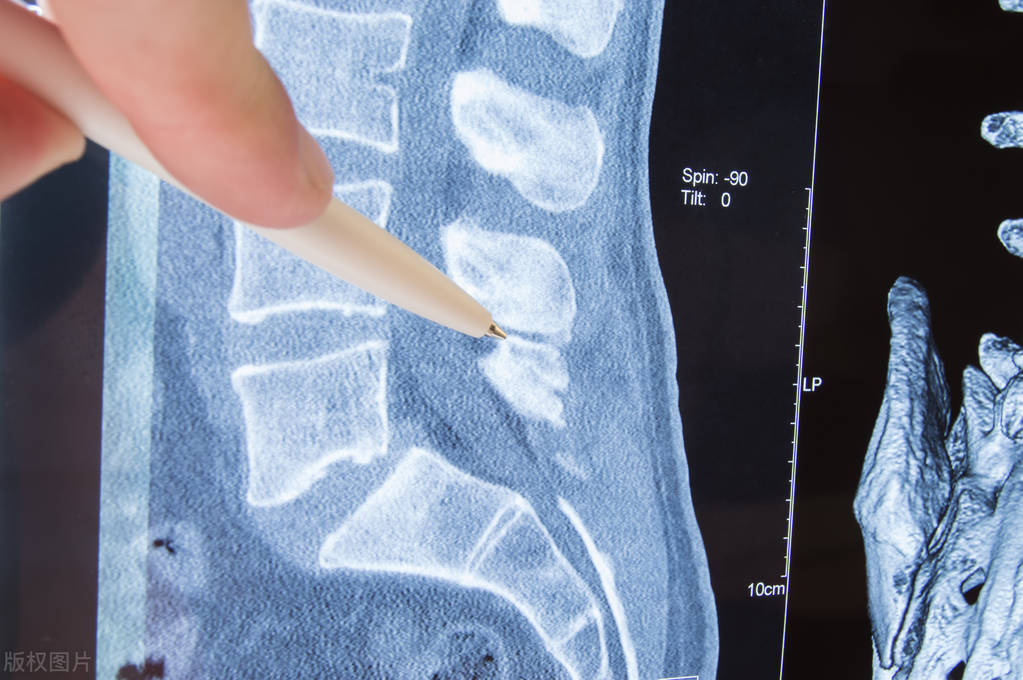

3 3 岁的一个男性患者,在医院检查出腰椎管狭窄症,腿疼不能久站,间歇性跛行,在当地进行了多次保守治疗,也有很多医生建议手术治疗,但患者始终害怕手术的后遗症和并发症,并且也觉得费用很高。

通过详细询问和查看多次的检查结果,这个患者属于轻度狭窄,是可以经过保守治疗来缓解的。